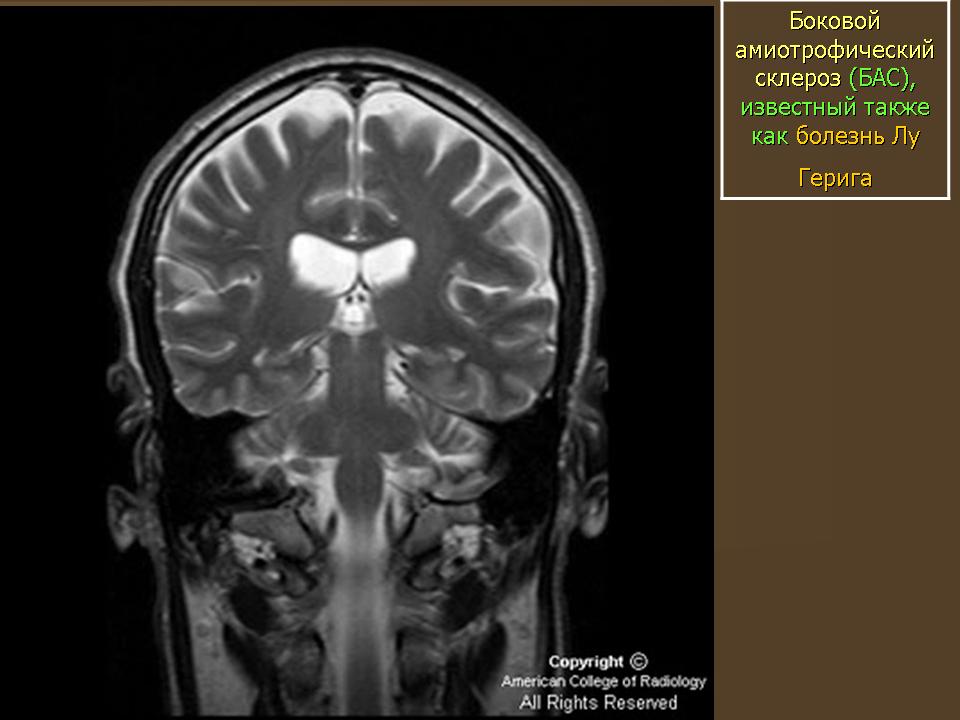

Официальное название заболевания - боковой ами-отрофический склероз (БАС), однако в США оно больше известно под названием «болезнь Лу Герига». Это прогрессирующее нейродегенеративное расстройство было диагностировано в 1939 г. у легендарного американского бейсболиста с таким именем, полевого игрока команды «Нью-Йорк Ян-киз», прожившего после появления первых симптомов всего два года. БАС начинается с повреждения нервных клеток, идущих от головного и спинного мозга к мышцам всех органов и тканей. Когда так называемые двигательные нейроны погибают, головной мозг оказывается не в состоянии управлять работой мышц, и наступает полный паралич.

Боковой амиотрофический склероз (БАС) - заболевание, при котором происходит дегенерация двигательных нейронов. В течение трех-пяти лет после появления первых симптомов наступает полный паралич, и больной умирает. В США самой известной жертвой БАС стал легендарный игрок бейсбольной команды «Нью-Йорк Янкиз» Лу Гериг.

Представление о том, что такое боковой амиотрофический склероз, дает само название болезни. «Амиотрофический» состоит из трех греческих слов. «А» - отрицание, «мио» - относящийся к мышцам, «трофика» - питание. Таким образом, мышцы у больных БАС испытывают дефицит питательных веществ, а потому атрофируются. Слово «боковой» указывает на область спинного мозга, в которой располагаются погибшие участки нервных клеток. С дегенерацией данной области происходит ее уплотнение («склероз» как раз и означает «затвердевание»). Возможно, самой ужасной особенностью заболевания является то, что больной не утрачивает умственны-ех способностей и осознает все, что с ним происходит.